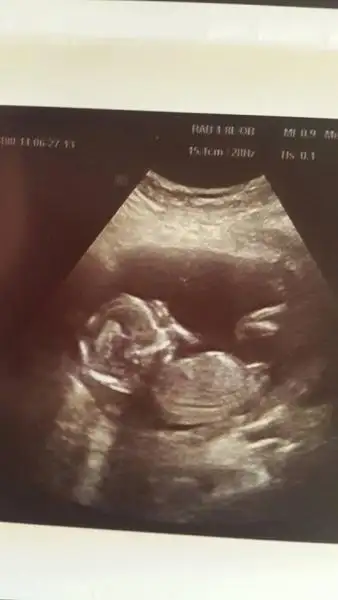

Benim 4 boyutlu değil ama bakabilirmisiniz nubuna. Şu an 13+0 Daha 10 gün var kontrole. Ilkinde 11 hafta 5 gün,ikincisinde 12 hafta 3 günlüktük.

$ImageUploadedByKadınlar Kulübü1403871674.160859.webp